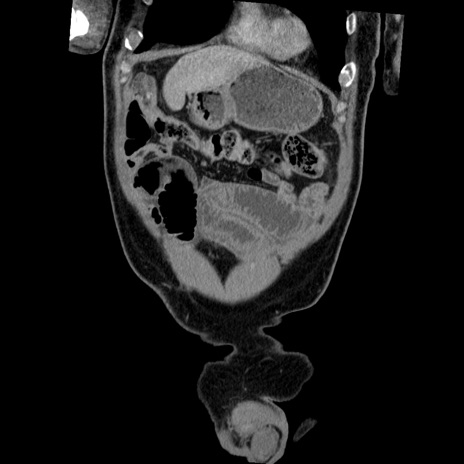

横断像

【症例】50歳代男性

【主訴】腹痛

【現病歴】AVMからの被殻出血のため回復期リハ病棟入院中。 本日午後3時頃急に下腹部痛が出現した。

【既往歴】AVM、被殻出血、虫垂炎、高血圧

【身体所見】意識晴明、左半身不全麻痺、会話の理解は良好、36.5°C、腹部:膨隆、全体に板状硬、下腹部正中に圧痛点あり、反跳痛-、筋性防御不明、右下腹部にope scar

【データ】WBC 9400、CRP 0.06